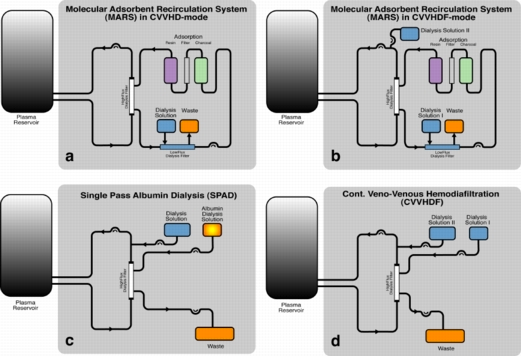

Conventional continuous veno-venous hemodiafiltration (CVVHDF) has been shown to be effective in the removal of water-soluble toxins. In order to clear the blood of albumin-bound, hydrophobic substances, additional adsorber or acceptor substances are necessary to enhance mass exchange. Albumin is one of the potential acceptor substances. Stange, Mitzner and co-workers introduced a detoxification system based on albumin dialysis - the Molecular Adsorbents Recirculation System (MARS). Separated from the patient’s blood by a high-flux hemodialysis filter, an albumin solution is circulated in a closed circuit. The albumin acts as the acceptor for the toxins and is partly regenerated by passing an anion exchanger and a charcoal adsorber in a closed circuit and is itself dialyzed by a standard dialysis solution in continuous veno-venous hemodialysis (CVVHD) or CVVHDF operation mode. In order to operate the system, additional hardware (MARS monitor) including a recirculation pump is necessary.

Conventional continuous veno-venous hemodiafiltration (CVVHDF) has been shown to be effective in the removal of water-soluble toxins. In order to clear the blood of albumin-bound, hydrophobic substances, additional adsorber or acceptor substances are necessary to enhance mass exchange. Albumin is one of the potential acceptor substances. Stange, Mitzner and co-workers introduced a detoxification system based on albumin dialysis - the Molecular Adsorbents Recirculation System (MARS). Separated from the patient’s blood by a high-flux hemodialysis filter, an albumin solution is circulated in a closed circuit. The albumin acts as the acceptor for the toxins and is partly regenerated by passing an anion exchanger and a charcoal adsorber in a closed circuit and is itself dialyzed by a standard dialysis solution in continuous veno-venous hemodialysis (CVVHD) or CVVHDF operation mode. In order to operate the system, additional hardware (MARS monitor) including a recirculation pump is necessary.

Single-pass albumin dialysis (SPAD) is a simple method of albumin dialysis using standard renal replacement therapy machines without an additional perfusion pump system: The patient’s blood flows through a circuit with a high-flux hollow fiber hemodiafilter, identical to that used in the MARS system. The other side of this membrane is cleansed with an albumin solution in counter-directional flow, which is discarded after passing the filter. CVVHDF can be performed in the first circuit via the same high-flux hollow fibers. Waiving of sorbent columns for regeneration of the adsorber-albumin, initial clinical application of SPAD was performed with higher concentrations of albumin in the dialysis fluid than in the MARS concept.

Single pass albumin dialysis (SPAD), the Molecular Adsorbents Recirculation System (MARS) and continuous veno-venous hemodiafiltration (CVVHDF) were compared in vitro with regard to detoxification capacity.